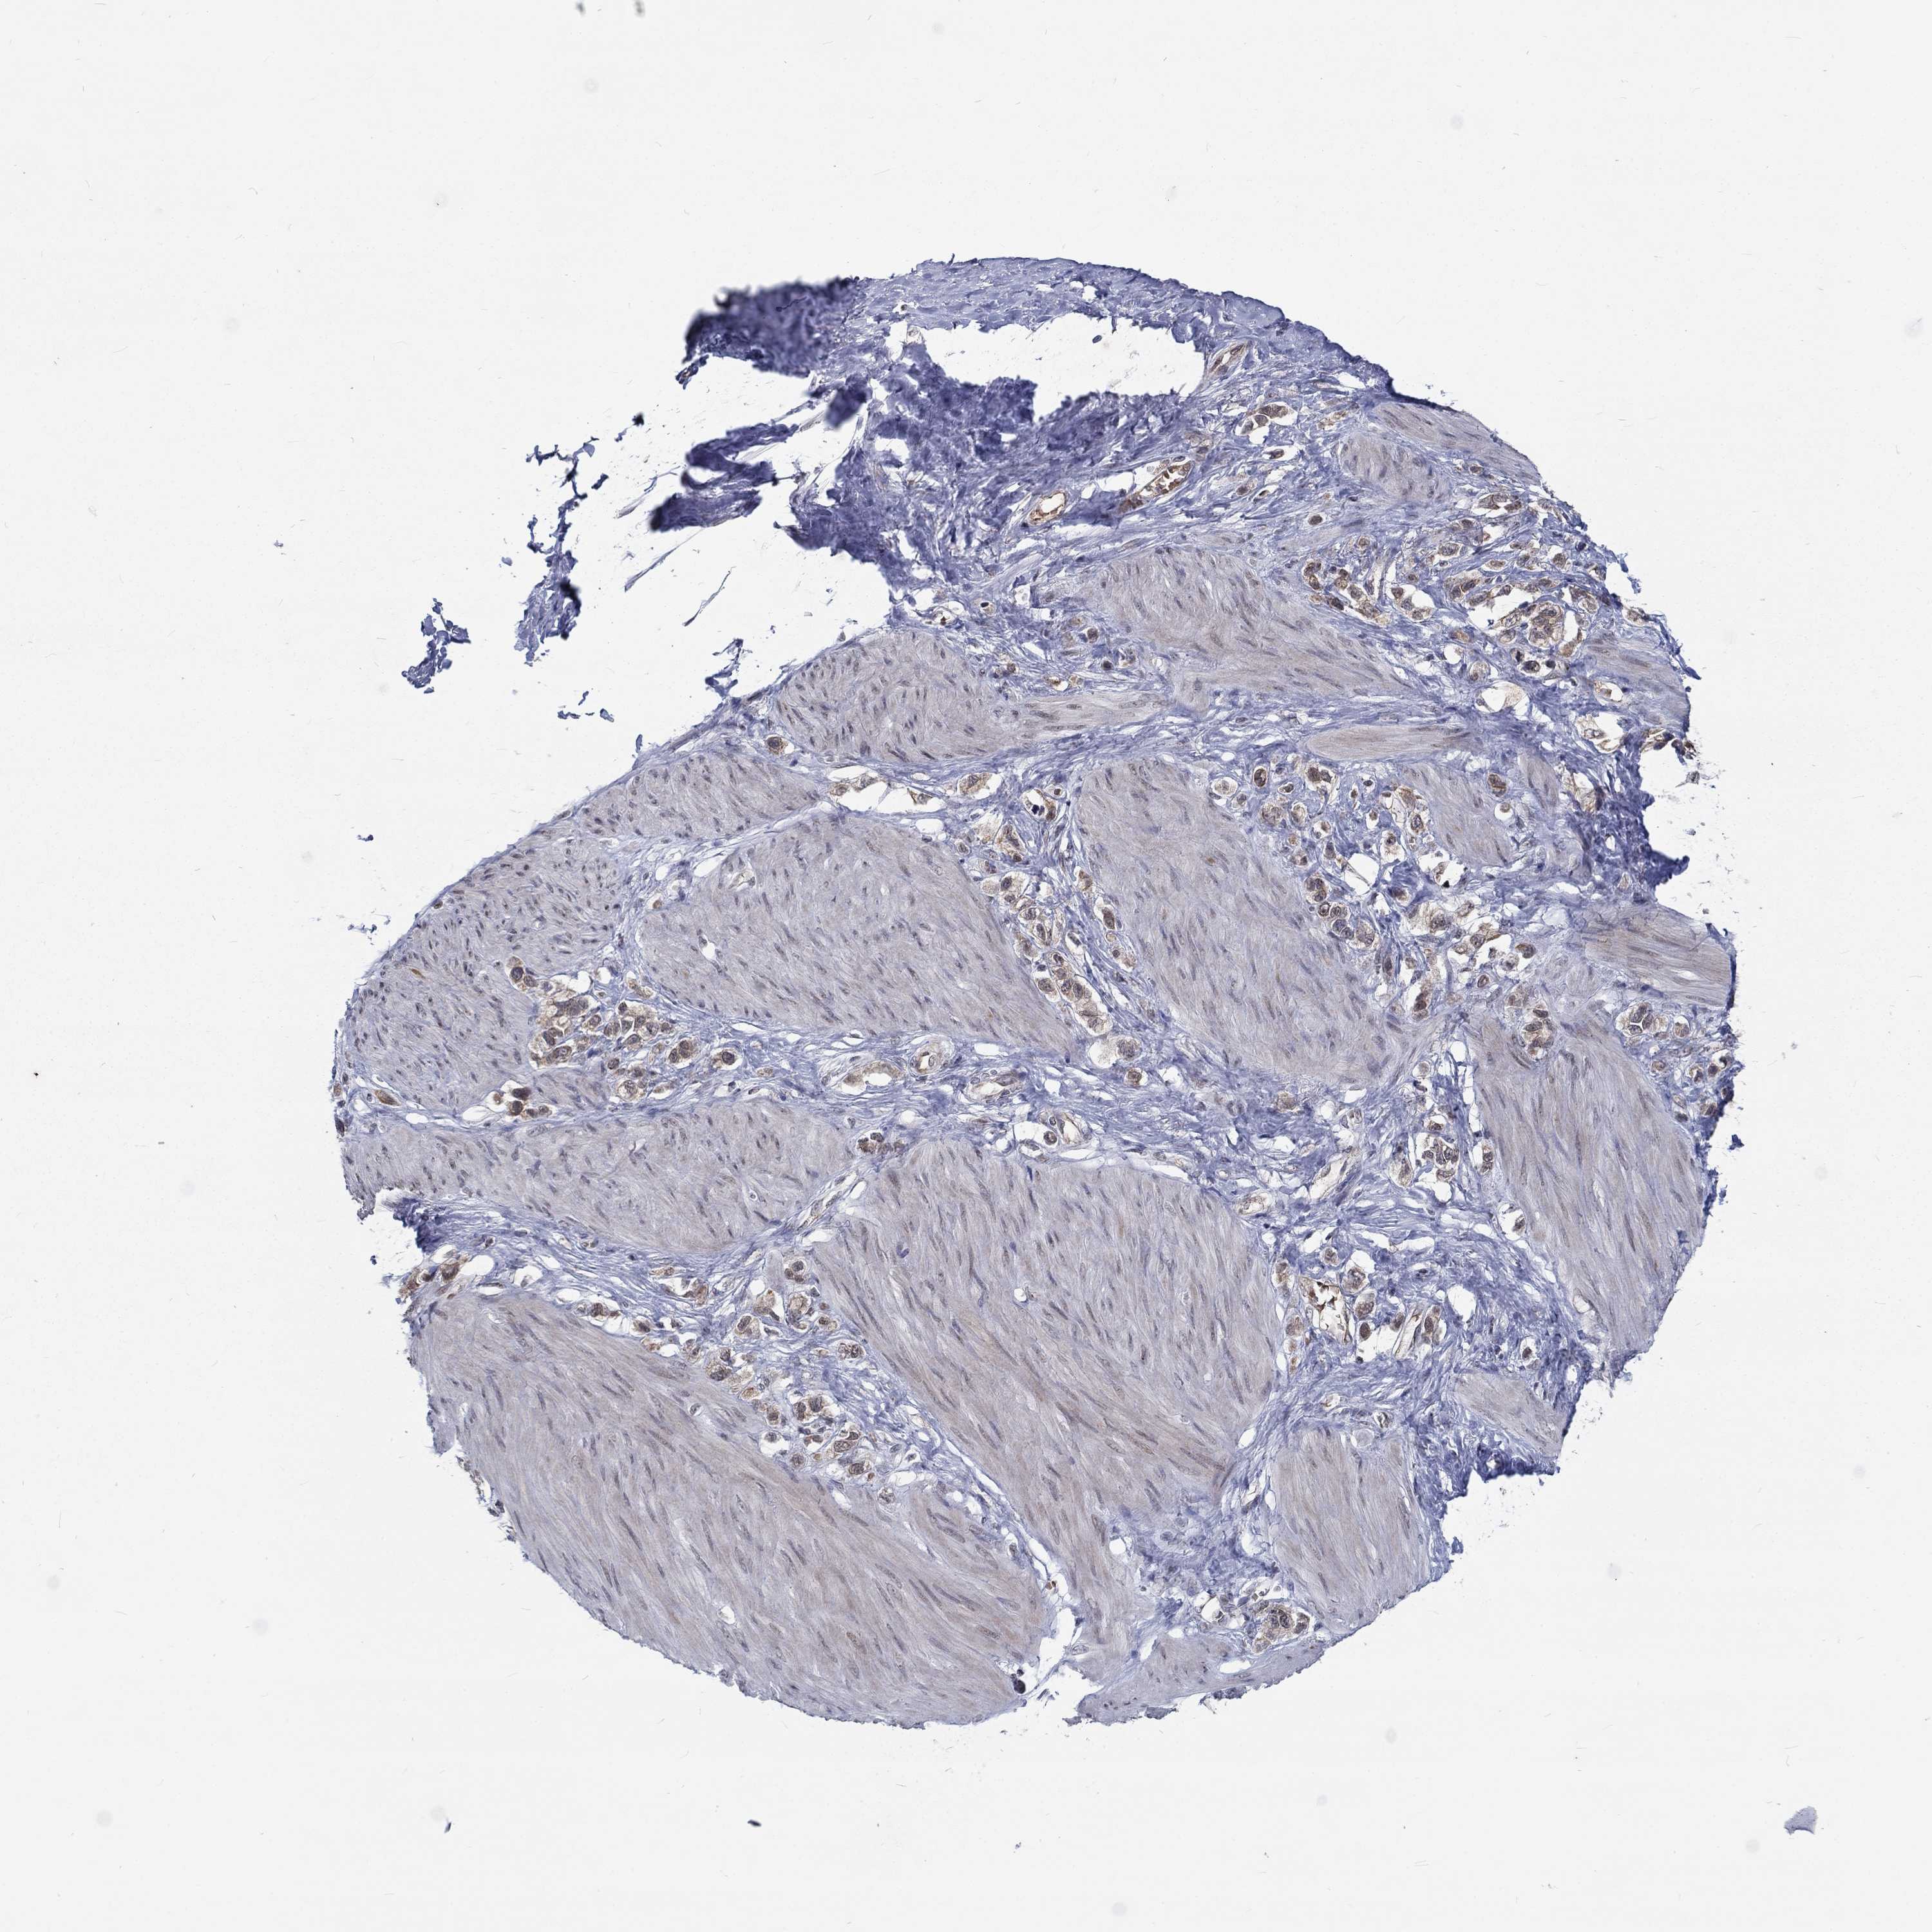

STOMACH CANCER - Protein expressioni

A mouse-over function shows sample information and annotation data. Click on an image to view it in a full screen mode. Samples can be filtered based on level of antibody staining by selecting one or several of the following categories: high, medium, low and not detected. The assay and annotation is described here.

Antibody stainingi

Antibody staining in the annotated cell types in the current human tissue is reported as not detected, low, medium, or high, based on conventional immunohistochemistry profiling in selected tissues. This score is based on the combination of the staining intensity and fraction of stained cells.

Each image is clickable and will lead to virtual microscopy that enables deeper exploration of all samples and also displays staining intensity scores, fraction scores and subcellular localization as well as patient and tissue information for each sample.

Antibody HPA077591

Staining

High

Medium

Low

Not detected

Intensity

Strong

Moderate

Weak

Negative

Quantity

>75%

75%-25%

<25%

None

Location

Nuclear

Cytoplasmic/membranous

Cytoplasmic/membranous,nuclear

Adenocarcinoma, NOS

Adenocarcinoma, High grade